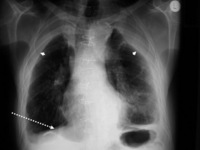

Posterior-anterior view of the chest with "mesa"-like pleural thickening of the left diaphragm and "in-profile" pleural thickening of the mid zones of both the left and right lungs

From the personal collection of Kenneth D. Rosenman MD